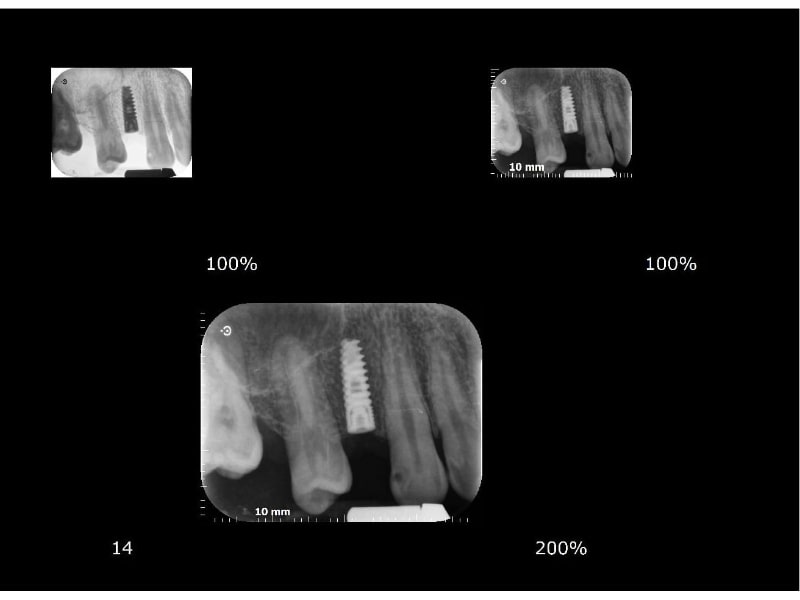

Implantologie